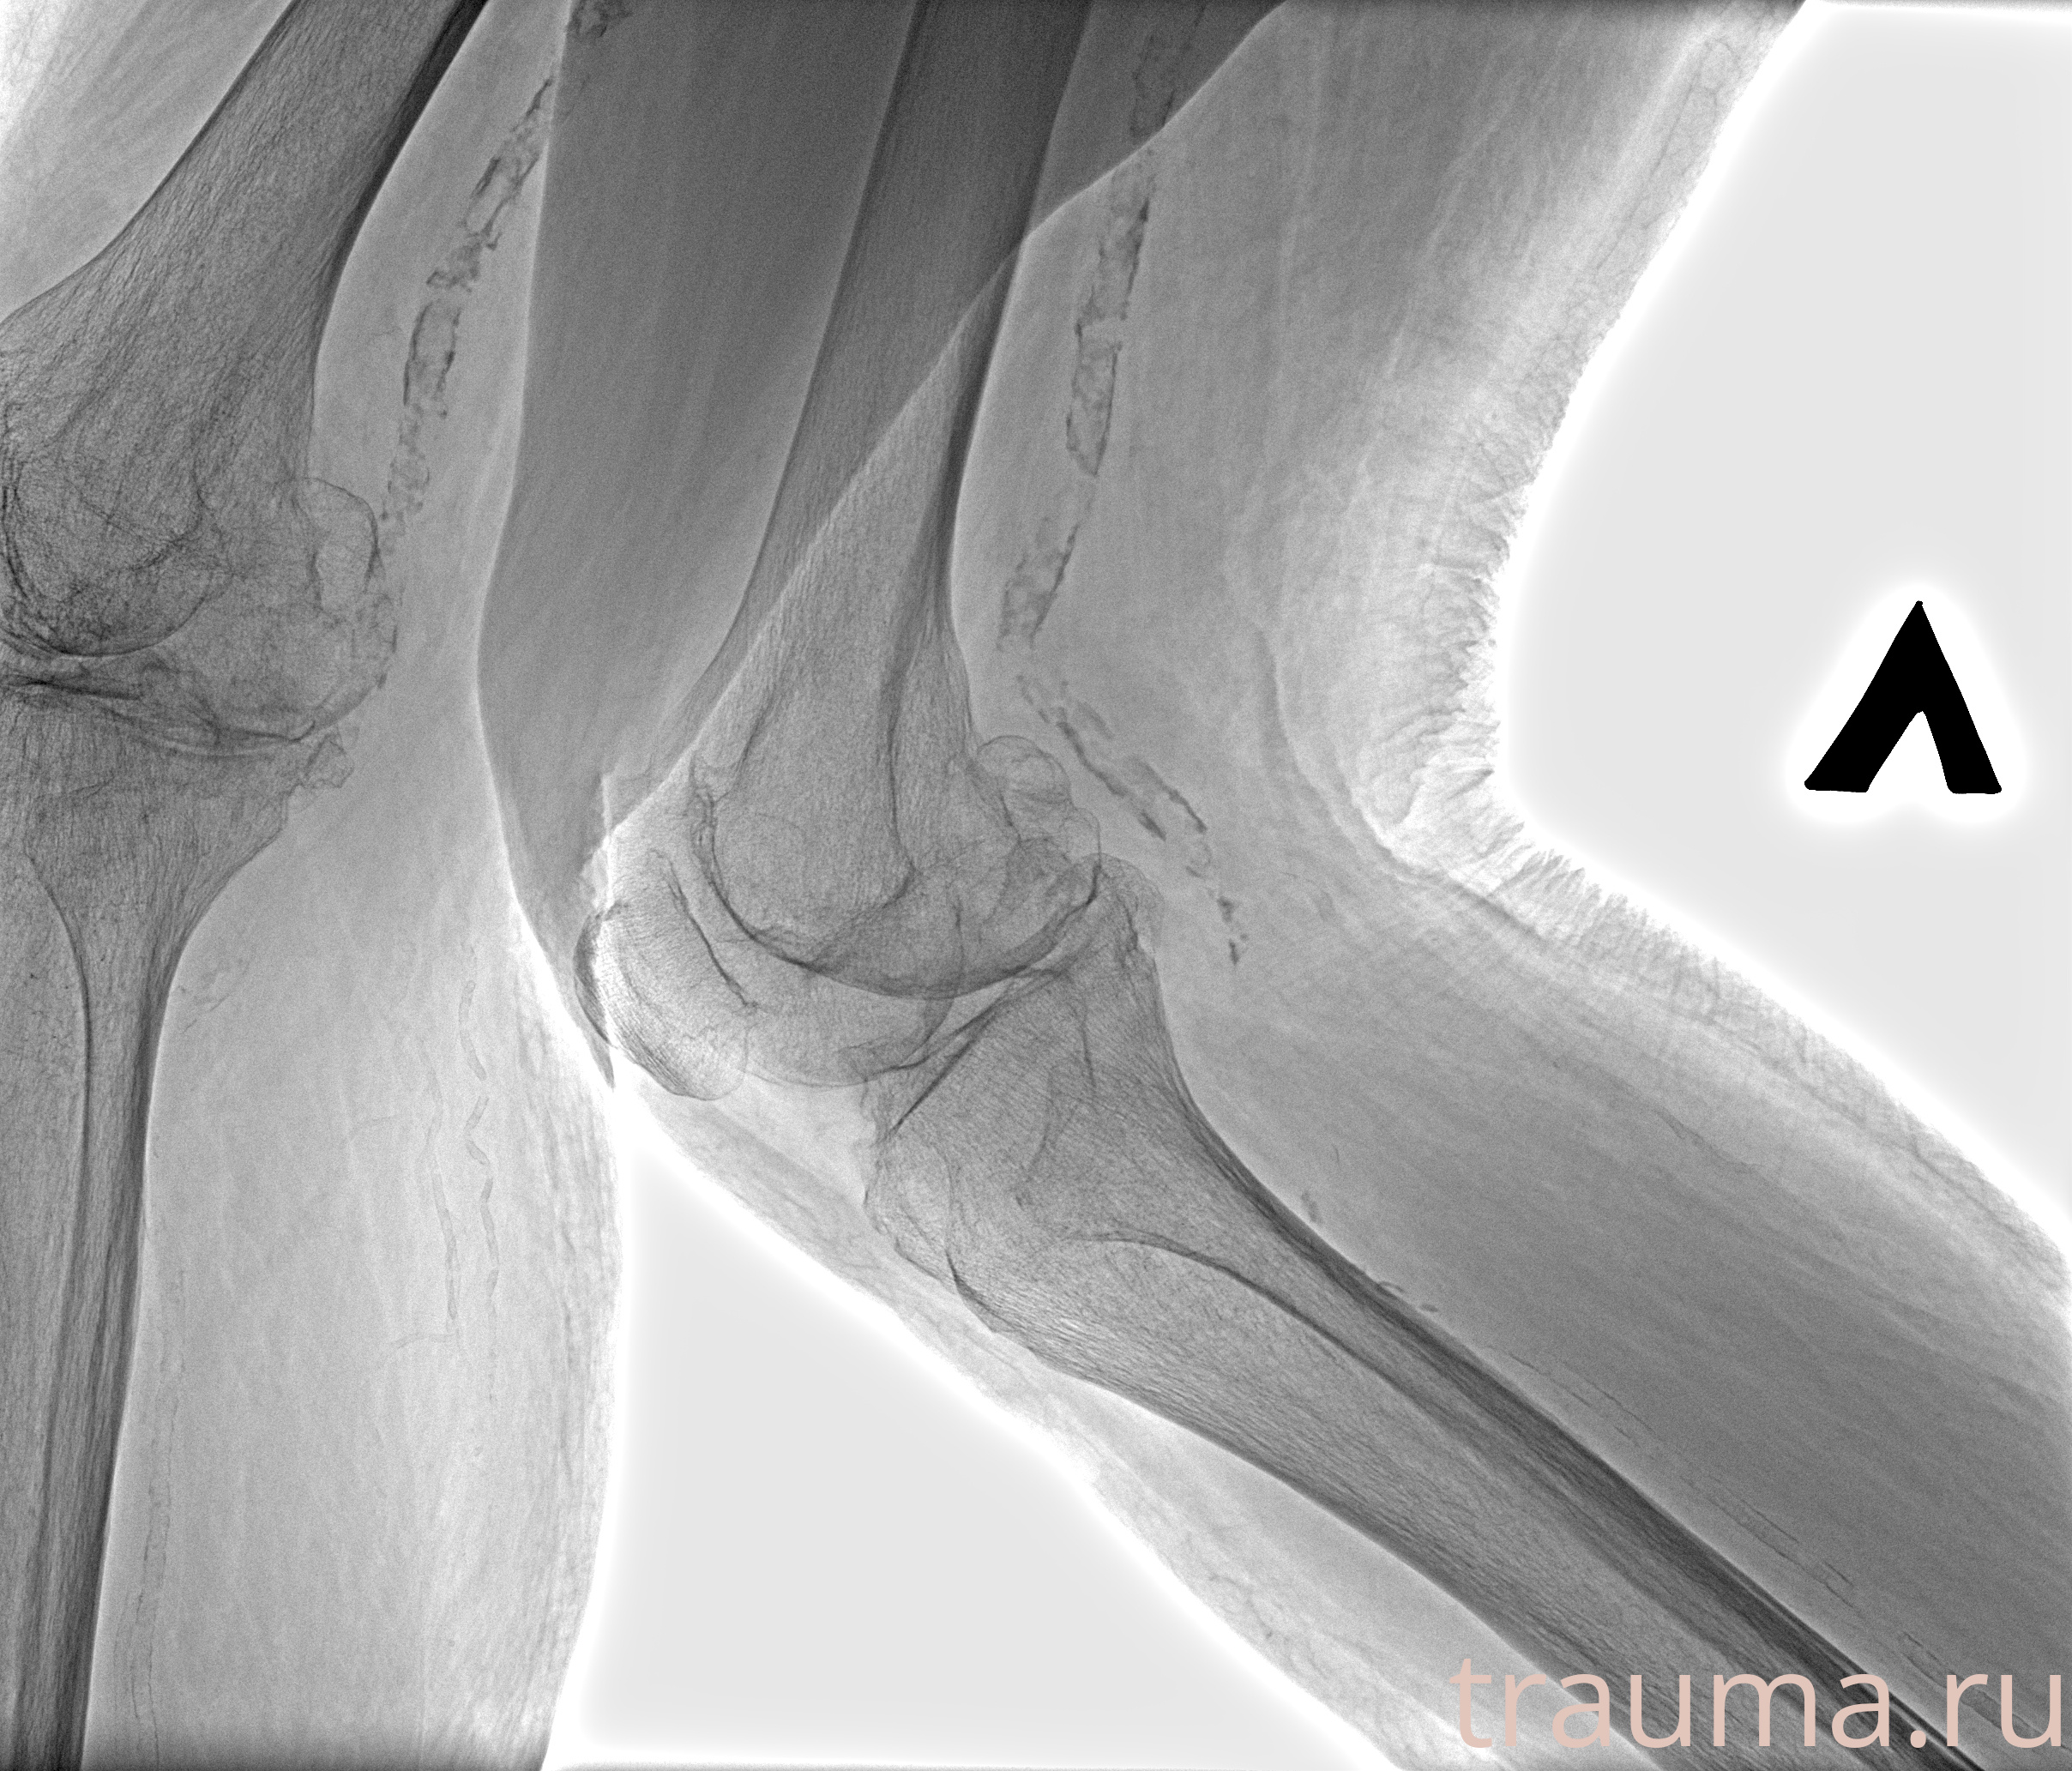

Рентген на дому: по вашему адресу приезжает врач-рентгенолог, травматолог-ортопед с мобильным рентгеновским аппаратом, проводит диагностику травмы или заболевания, делает необходимые рентгенограммы, дает рекомендации по дальнейшему лечению. Получить качественные снимки в домашних условиях возможно благодаря уникальной методике, разработанной МосРентген Центром для института  Склифосовского